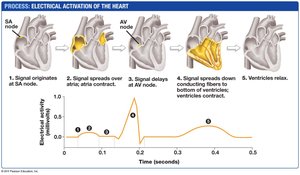

Cardiac Cycle and Blood Flow

The cardiac cycle consists of alternating periods of contraction (systole) and relaxation (diastole), ensuring unidirectional blood flow through the heart and to the body.

Systole: Ventricular contraction pumps blood into arteries.

Diastole: Heart relaxes and fills with blood.

Valves prevent backflow and produce the characteristic "lub-dup" heart sounds.

Electrical Control of the Heart

The heart's rhythmic contractions are initiated and coordinated by pacemaker cells in the sinoatrial (SA) node, with signals relayed through the atrioventricular (AV) node and specialized conduction fibers.